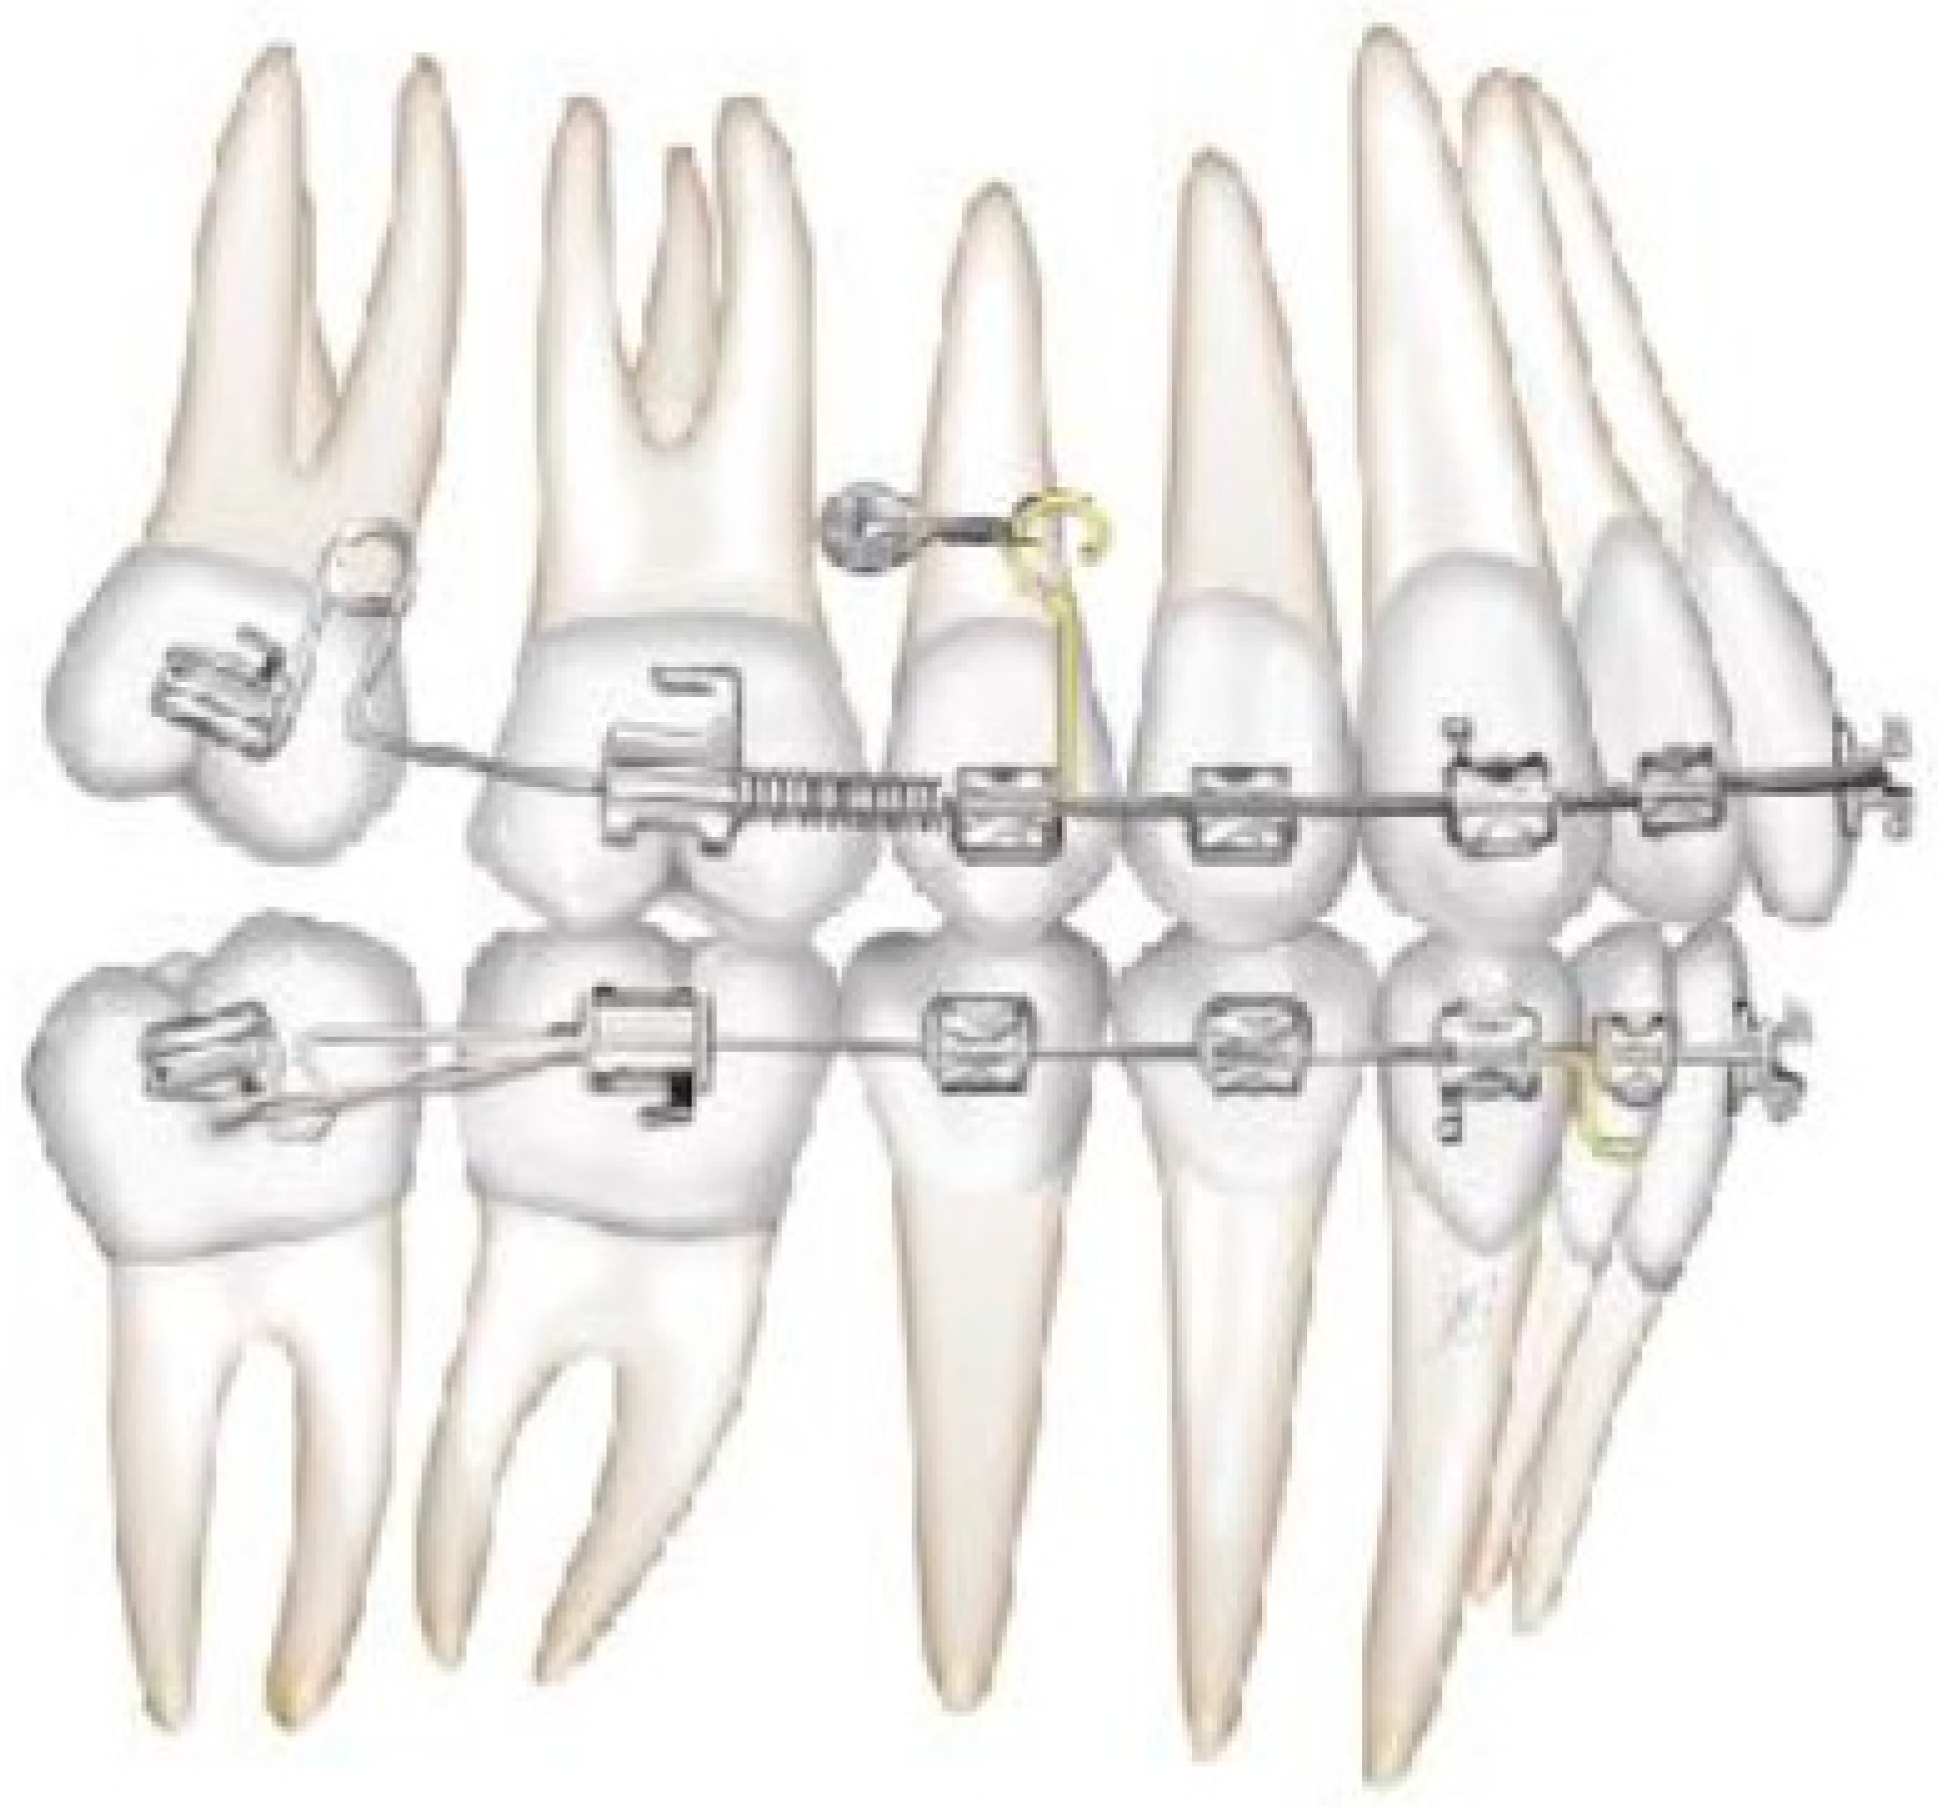

2.2. Molars’ and Premolars’ Distalization

2.3. Canine and Incisor Distalization